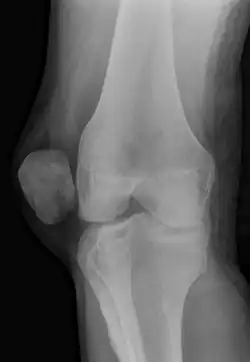

| X-ray showing a patellar dislocation, with the patella out to the side. | |